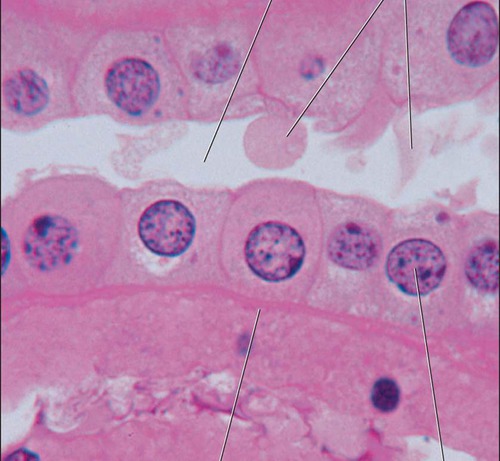

simple cuboidal

single layer of cube shaped cells; functions in tubular secretion and absorption